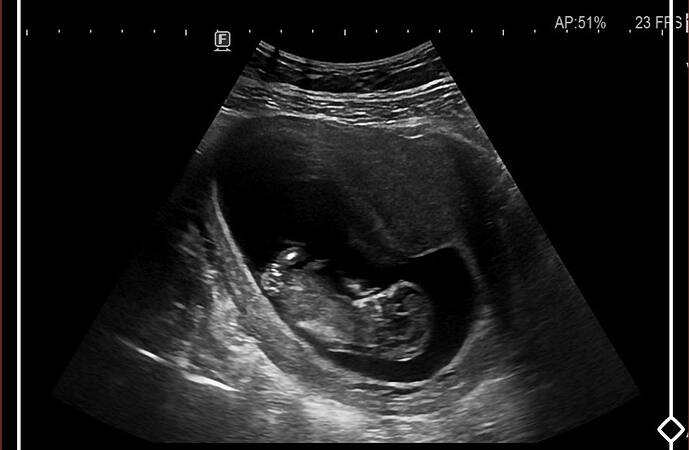

Benim kese böyleydi oğlum oldu ama bilemiyorum rabbim sağlıkla mutlulukla versin inşallah

Benim keseme benziyor bence erkek